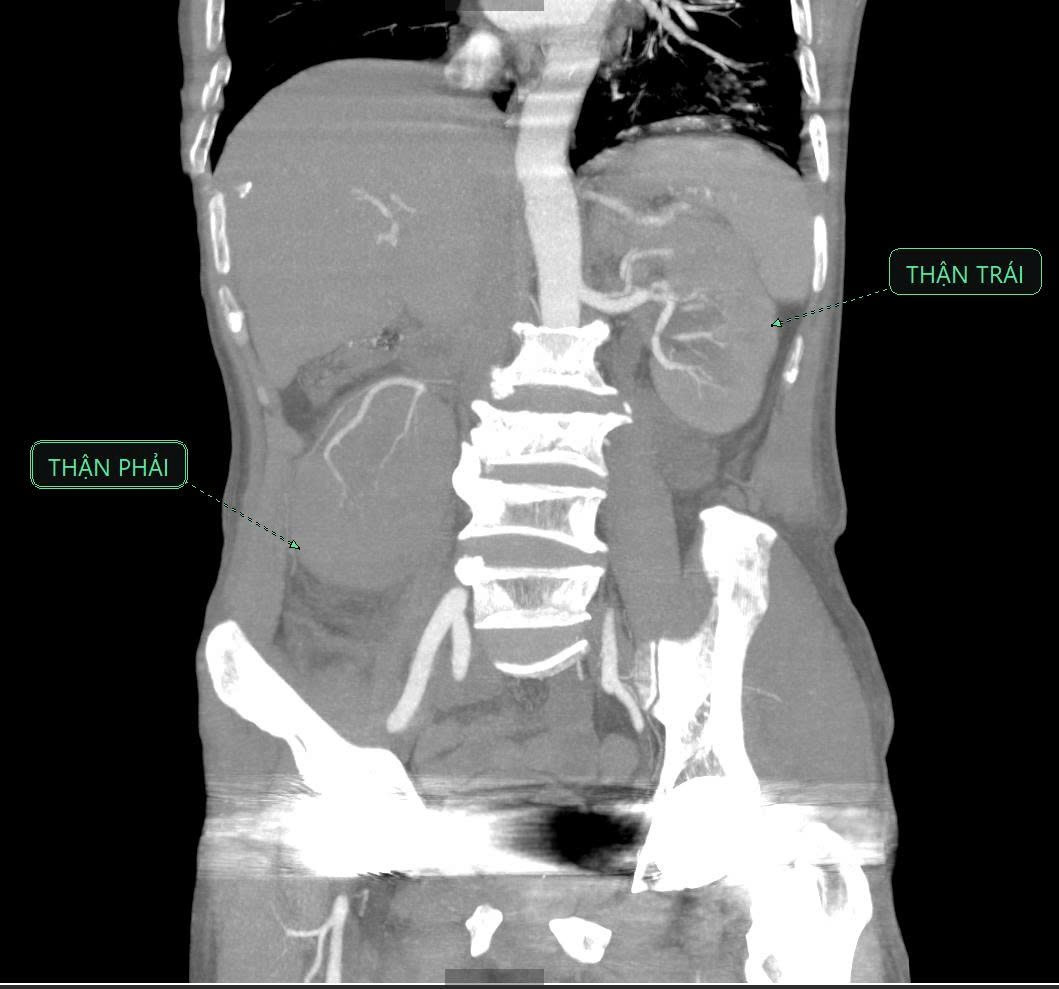

Các bác sĩ đã nhanh chóng thực hiện các cận lâm sàng cần thiết. Kết quả chụp CT-Scanner ổ bụng ghi nhận viêm thận – bể thận phải, thận phải lạc chỗ và giãn đài bể thận trái.

Hình ảnh chụp Cắt lớp vi tính có tiêm thuốc cản quang: Thận phải lạc chỗ, nhu mô thận phải ngấm thải thuốc kém hơn thận trái, bể thận xoay ngoài, nhu mô thận có hình ảnh các ổ không ngấm thuốc (quan sát rõ ở các thì tĩnh mạch và thì muộn) - Ảnh BVCC